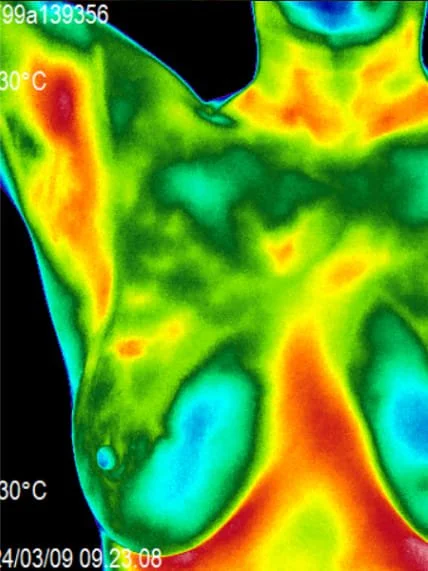

A female client presented with high inflammatory patterns across the chest, lymph zones, and breast tissue on initial thermography - indicating immune stress and hormonal imbalance. After targeted drainage, detox, and endocrine support, follow-up imaging showed a dramatic reduction in vascular heat and inflammatory hotspots, confirming systemic calm and breast tissue normalization.